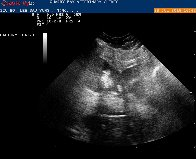

Chest X-ray: Determines size of heart, fluid around heart, possible abnormal masses grow.

Electrocardiography (ECG): Determines cardiac electrical impulses and measures arrhythmias.

Echocardiography: Detects fluid or masses around the heart, heart valve function, heart muscle and pericardial health.